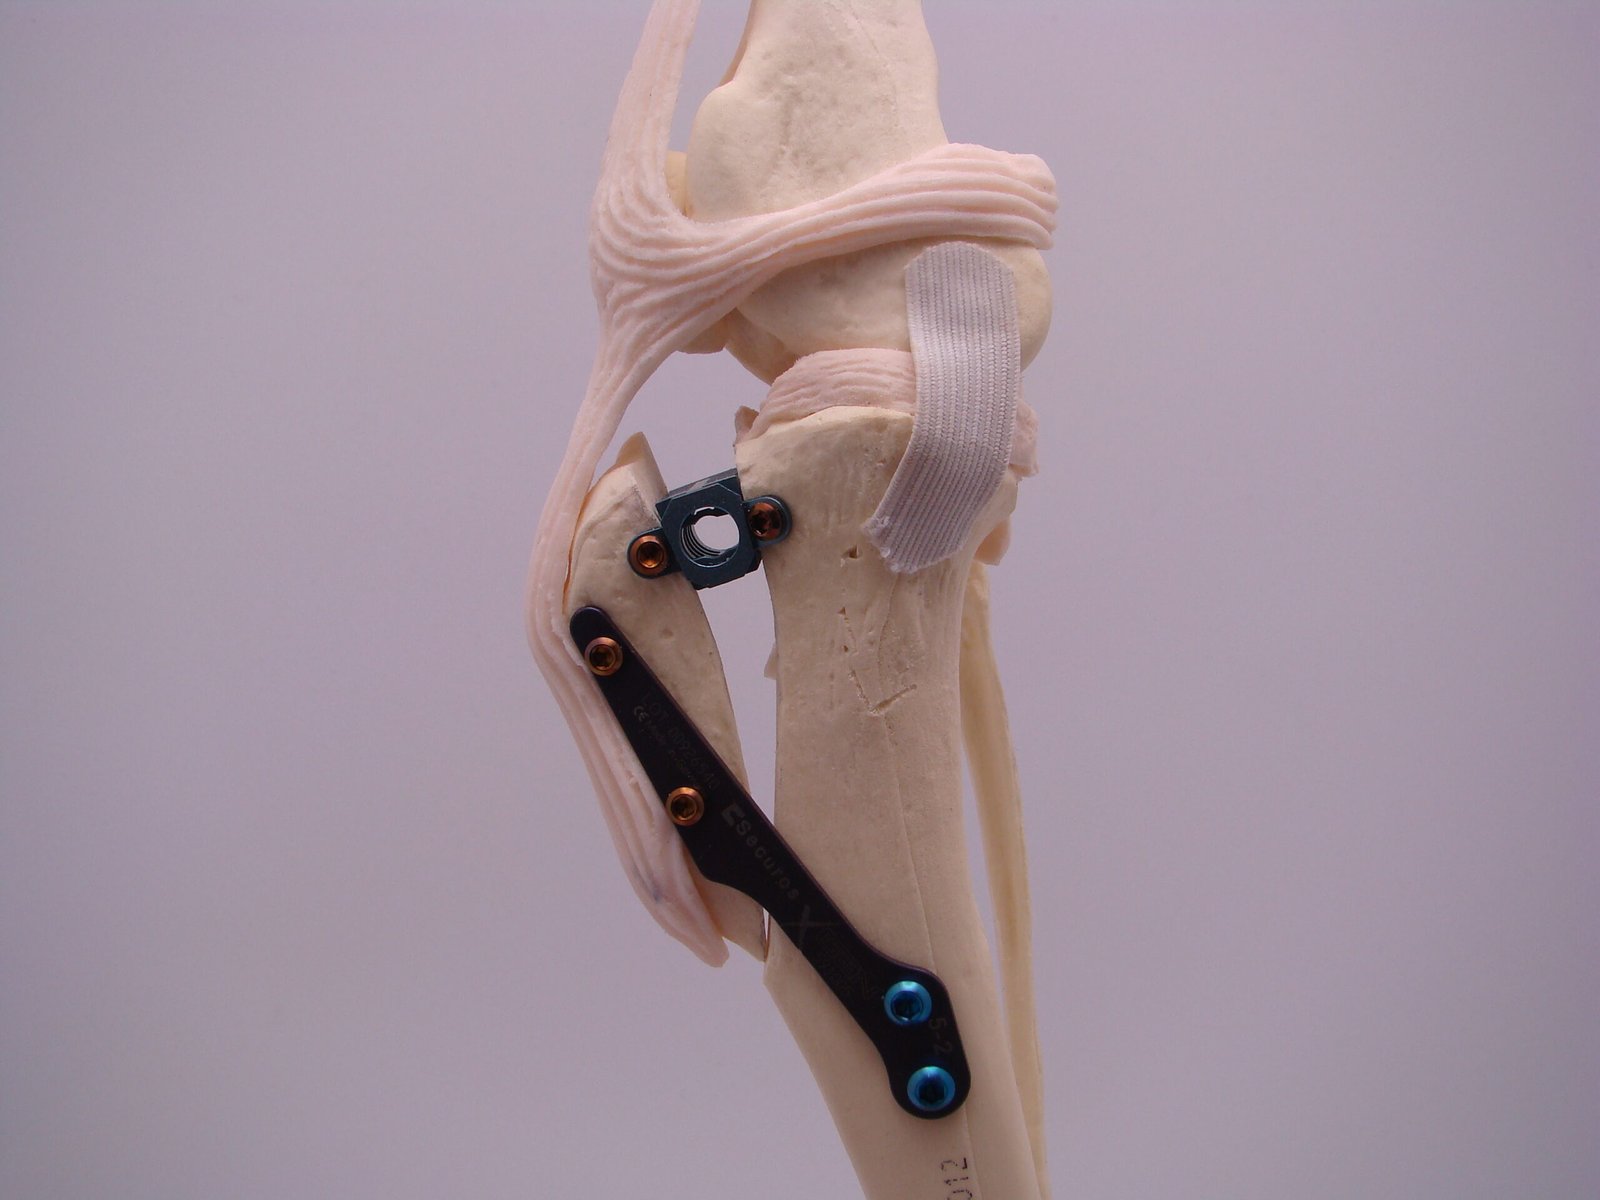

This course serves as an introduction to the management of some of the more common elbow pathologies currently encountered. It aims to guide attendees through the decision-making processes associated with elbow pain, focusing on the management of elbow dysplasia and humeral intercondylar fissure during the morning session.

In the afternoon, there will be a wet lab where attendees can practice screw placement. This session will also cover both medial and lateral approaches to the humeral condyle, as well as the placement of implants to effectively treat these fractures. This course includes both a wet and dry lab.